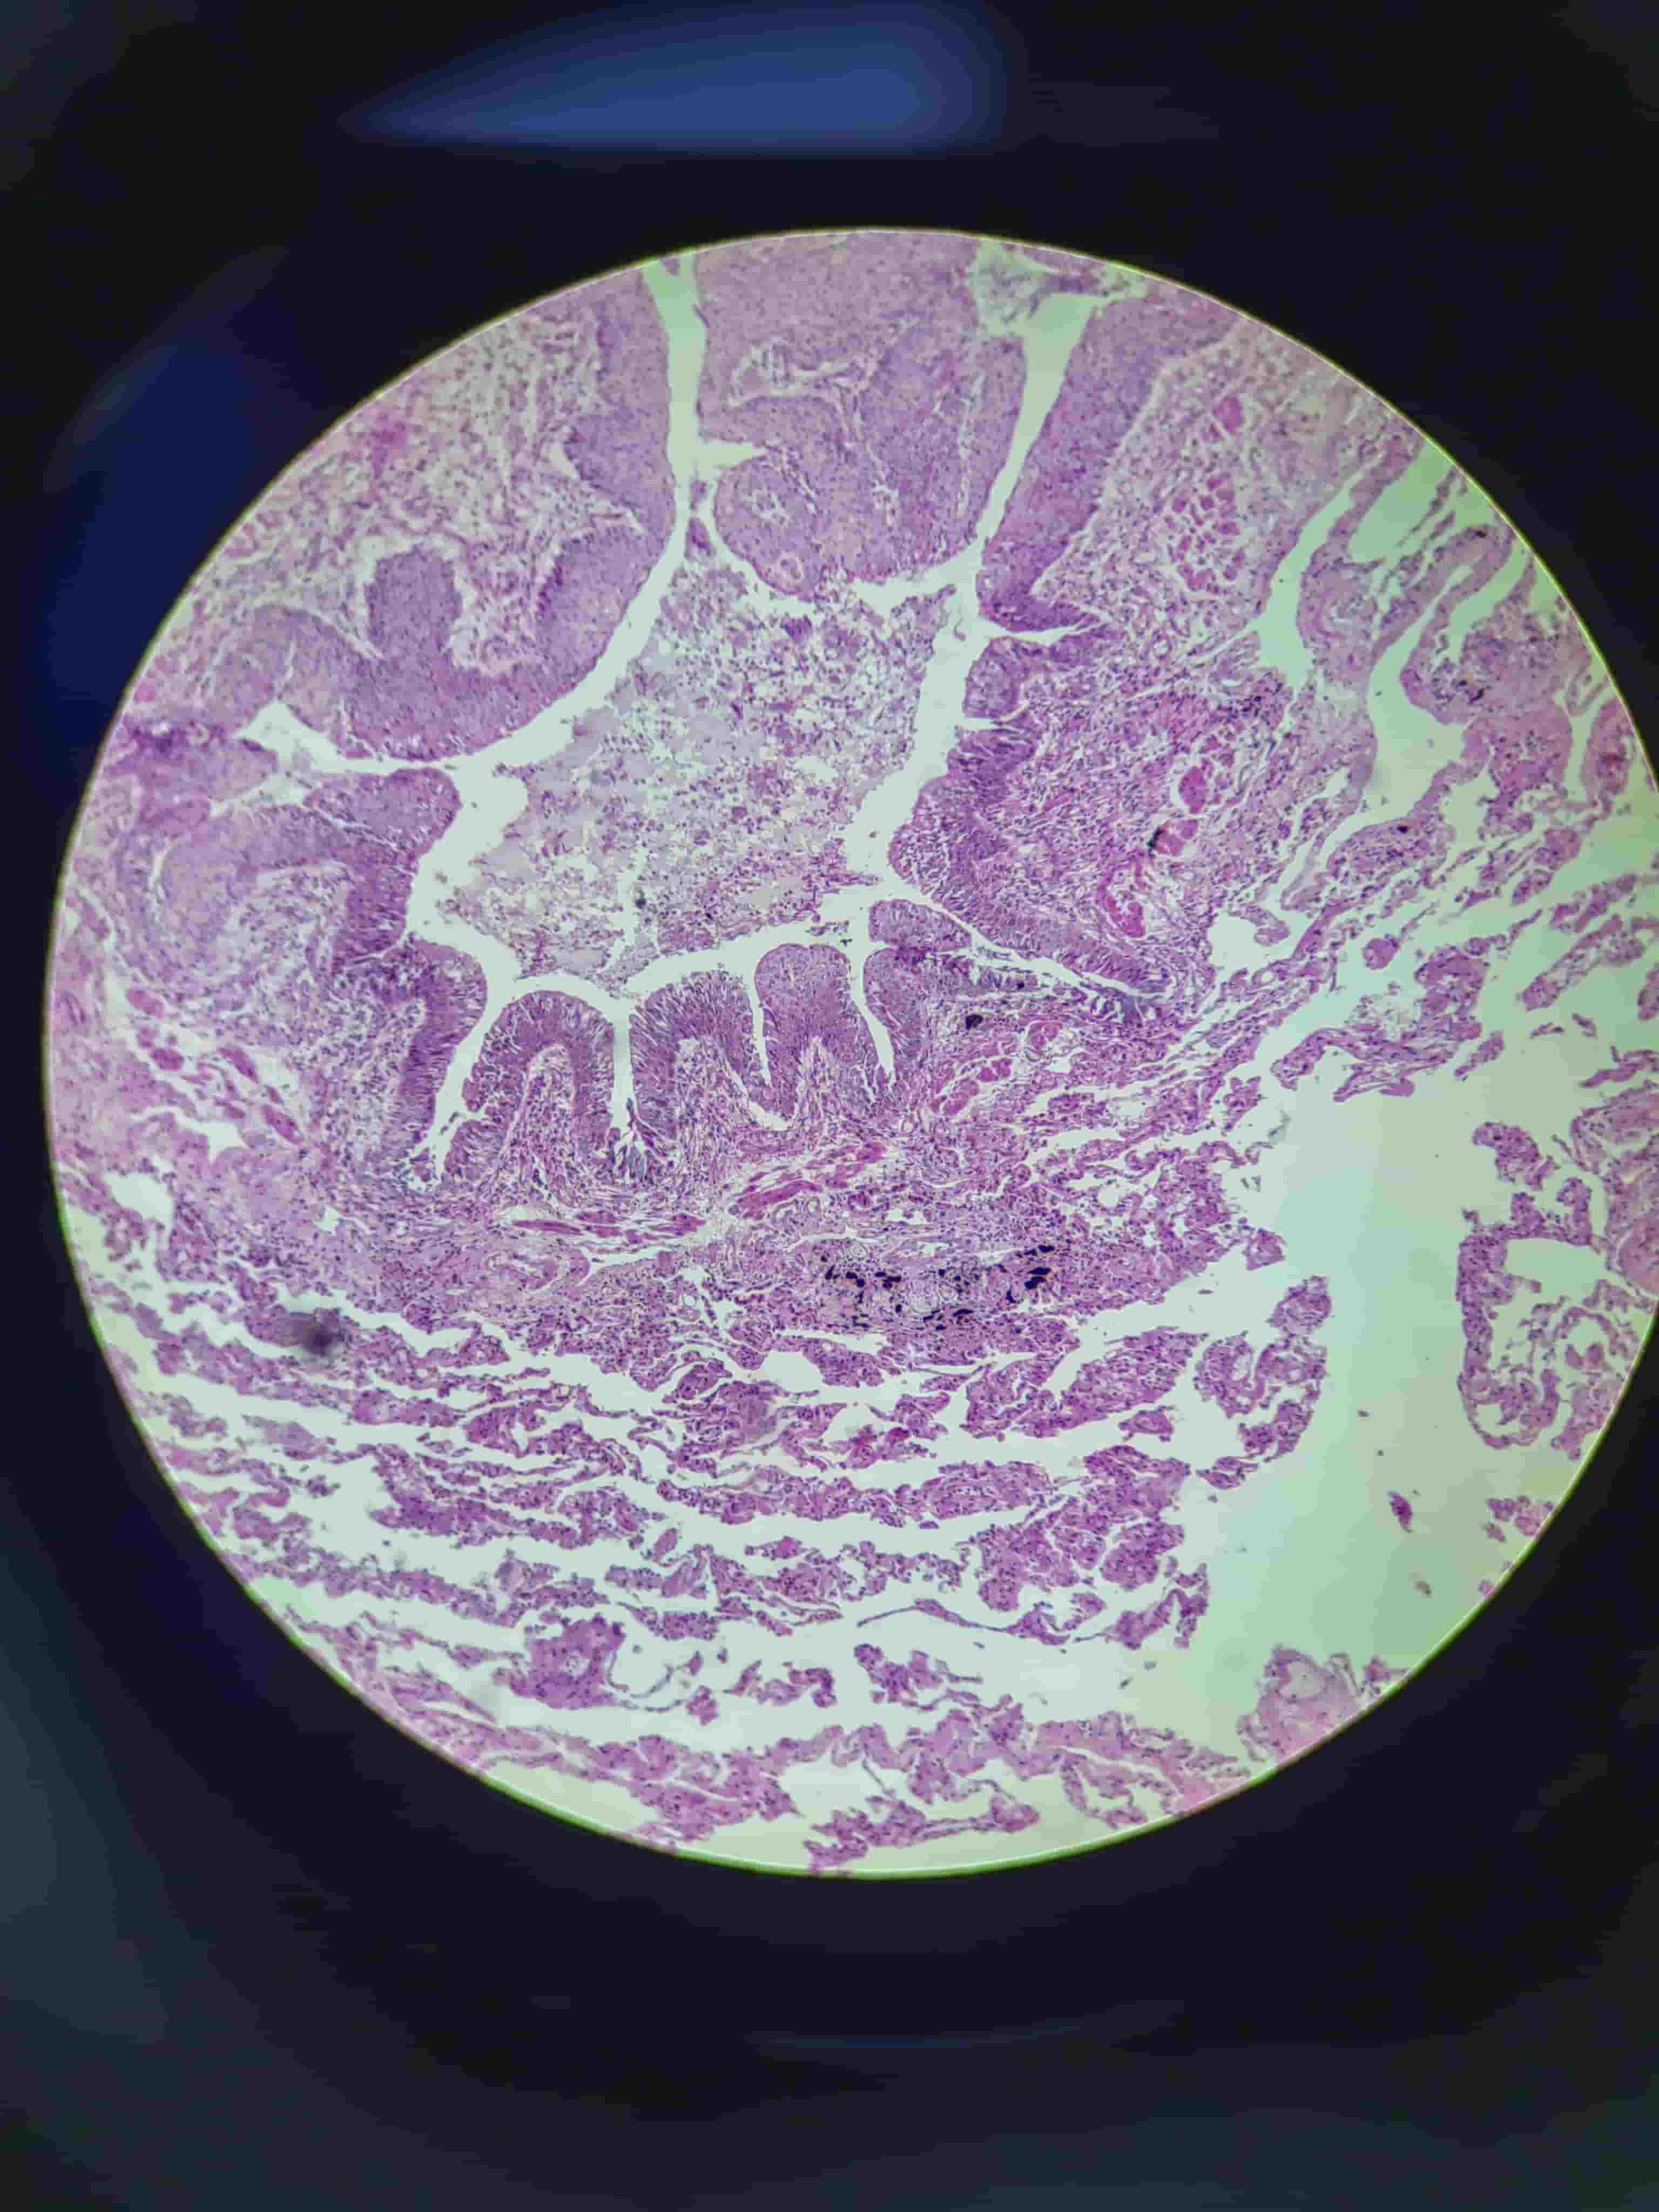

结肠腺癌